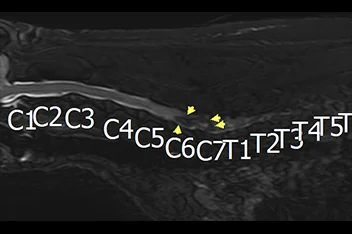

• 경추 디스크 MRI

• 흉요추 디스크 MRI